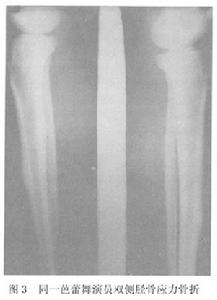

在體育運動和軍事訓練中,應力骨折最常見的部位是脛骨,多數報導占所有應力骨折的半數以上,劉大雄報導占78.0%,黃昌林報導達83.3%。脛骨應力骨折的發病部位因運動項目的不同而各異,行軍訓練的新兵群體多發生在近段脛骨的後內側(圖1)中長跑運動員好發於脛骨中下段的後側(圖2),而芭蕾舞演員則多發生在脛骨中段的前側(圖3)。

圖3應力骨折重在預防近年來國內外對運動和訓練中應力骨折預防的研究報告很多,大致有以下幾個方面